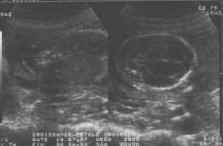

Coupes sagittales : parcourant tout le rachis (cliché gauche).

Coupes transversales : vertèbre par vertèbre (cliché droit).

- Sur une coupe sagittale stricte : corps vertébraux, canal rachidien (deux fines lignes parallèles) suivi jusqu’au cône terminal (effilé) et intégrité du revêtement cutané.

- Sur une coupe para-sagittale : corps vertébraux et lames latérales.

de dedans en dehors, corps vertébraux, canal rachidien, lames latérales, revêtement cutané.

Coupes frontales : Deux lignes parallèles discontinues régulièrement, correspondant aux lames latérales, au milieu le canal rachidien.